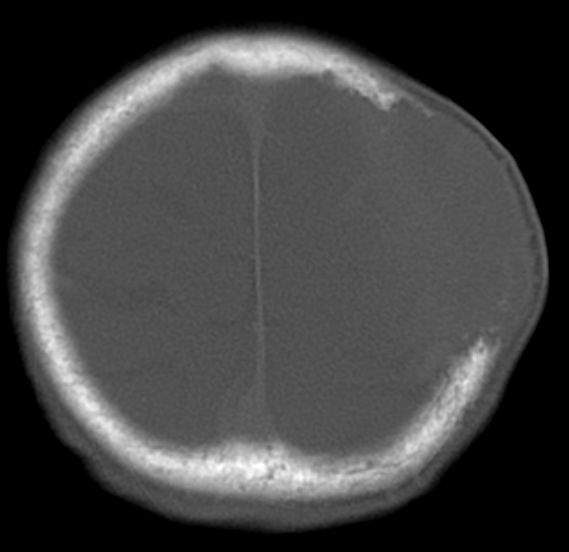

74-jährige Patientin, die 17 Jahre nach

Bronchialkarzinom rechts und 9 Jahre nach Plattenepithelkarzinom der linken

Lunge Hirn- und Knochenmetastasen entwickelte. ![]() |

Das gleiche Bild im Knochenfenster.![]() | ||